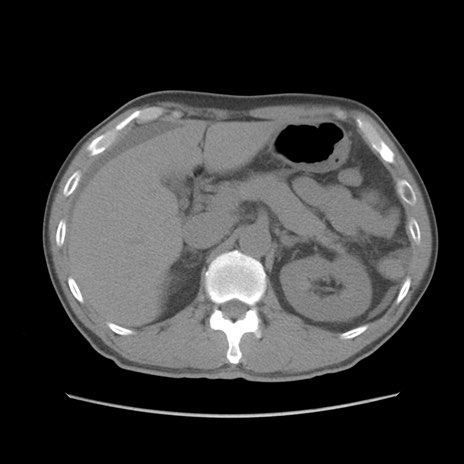

症例56 CT(横断像)